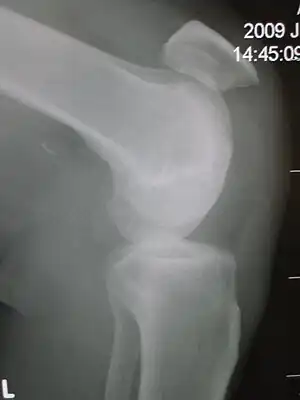

Patellar tendon rupture showing a marked distance between the tibial tuberosity and the bottom of the knee cap.

Patellar tendon rupture

Patellar tendon rupture can usually be diagnosed by physical examination. The most common signs are: tenderness, the tendon's loss of tone, loss of ability to raise the straight leg and observation of the high-riding patella. Radiographically, patella alta can be detected using the Insall and Salvati method when the patella is shorter than its tendon. Partial tears may be visualized using MRI scans.[4]